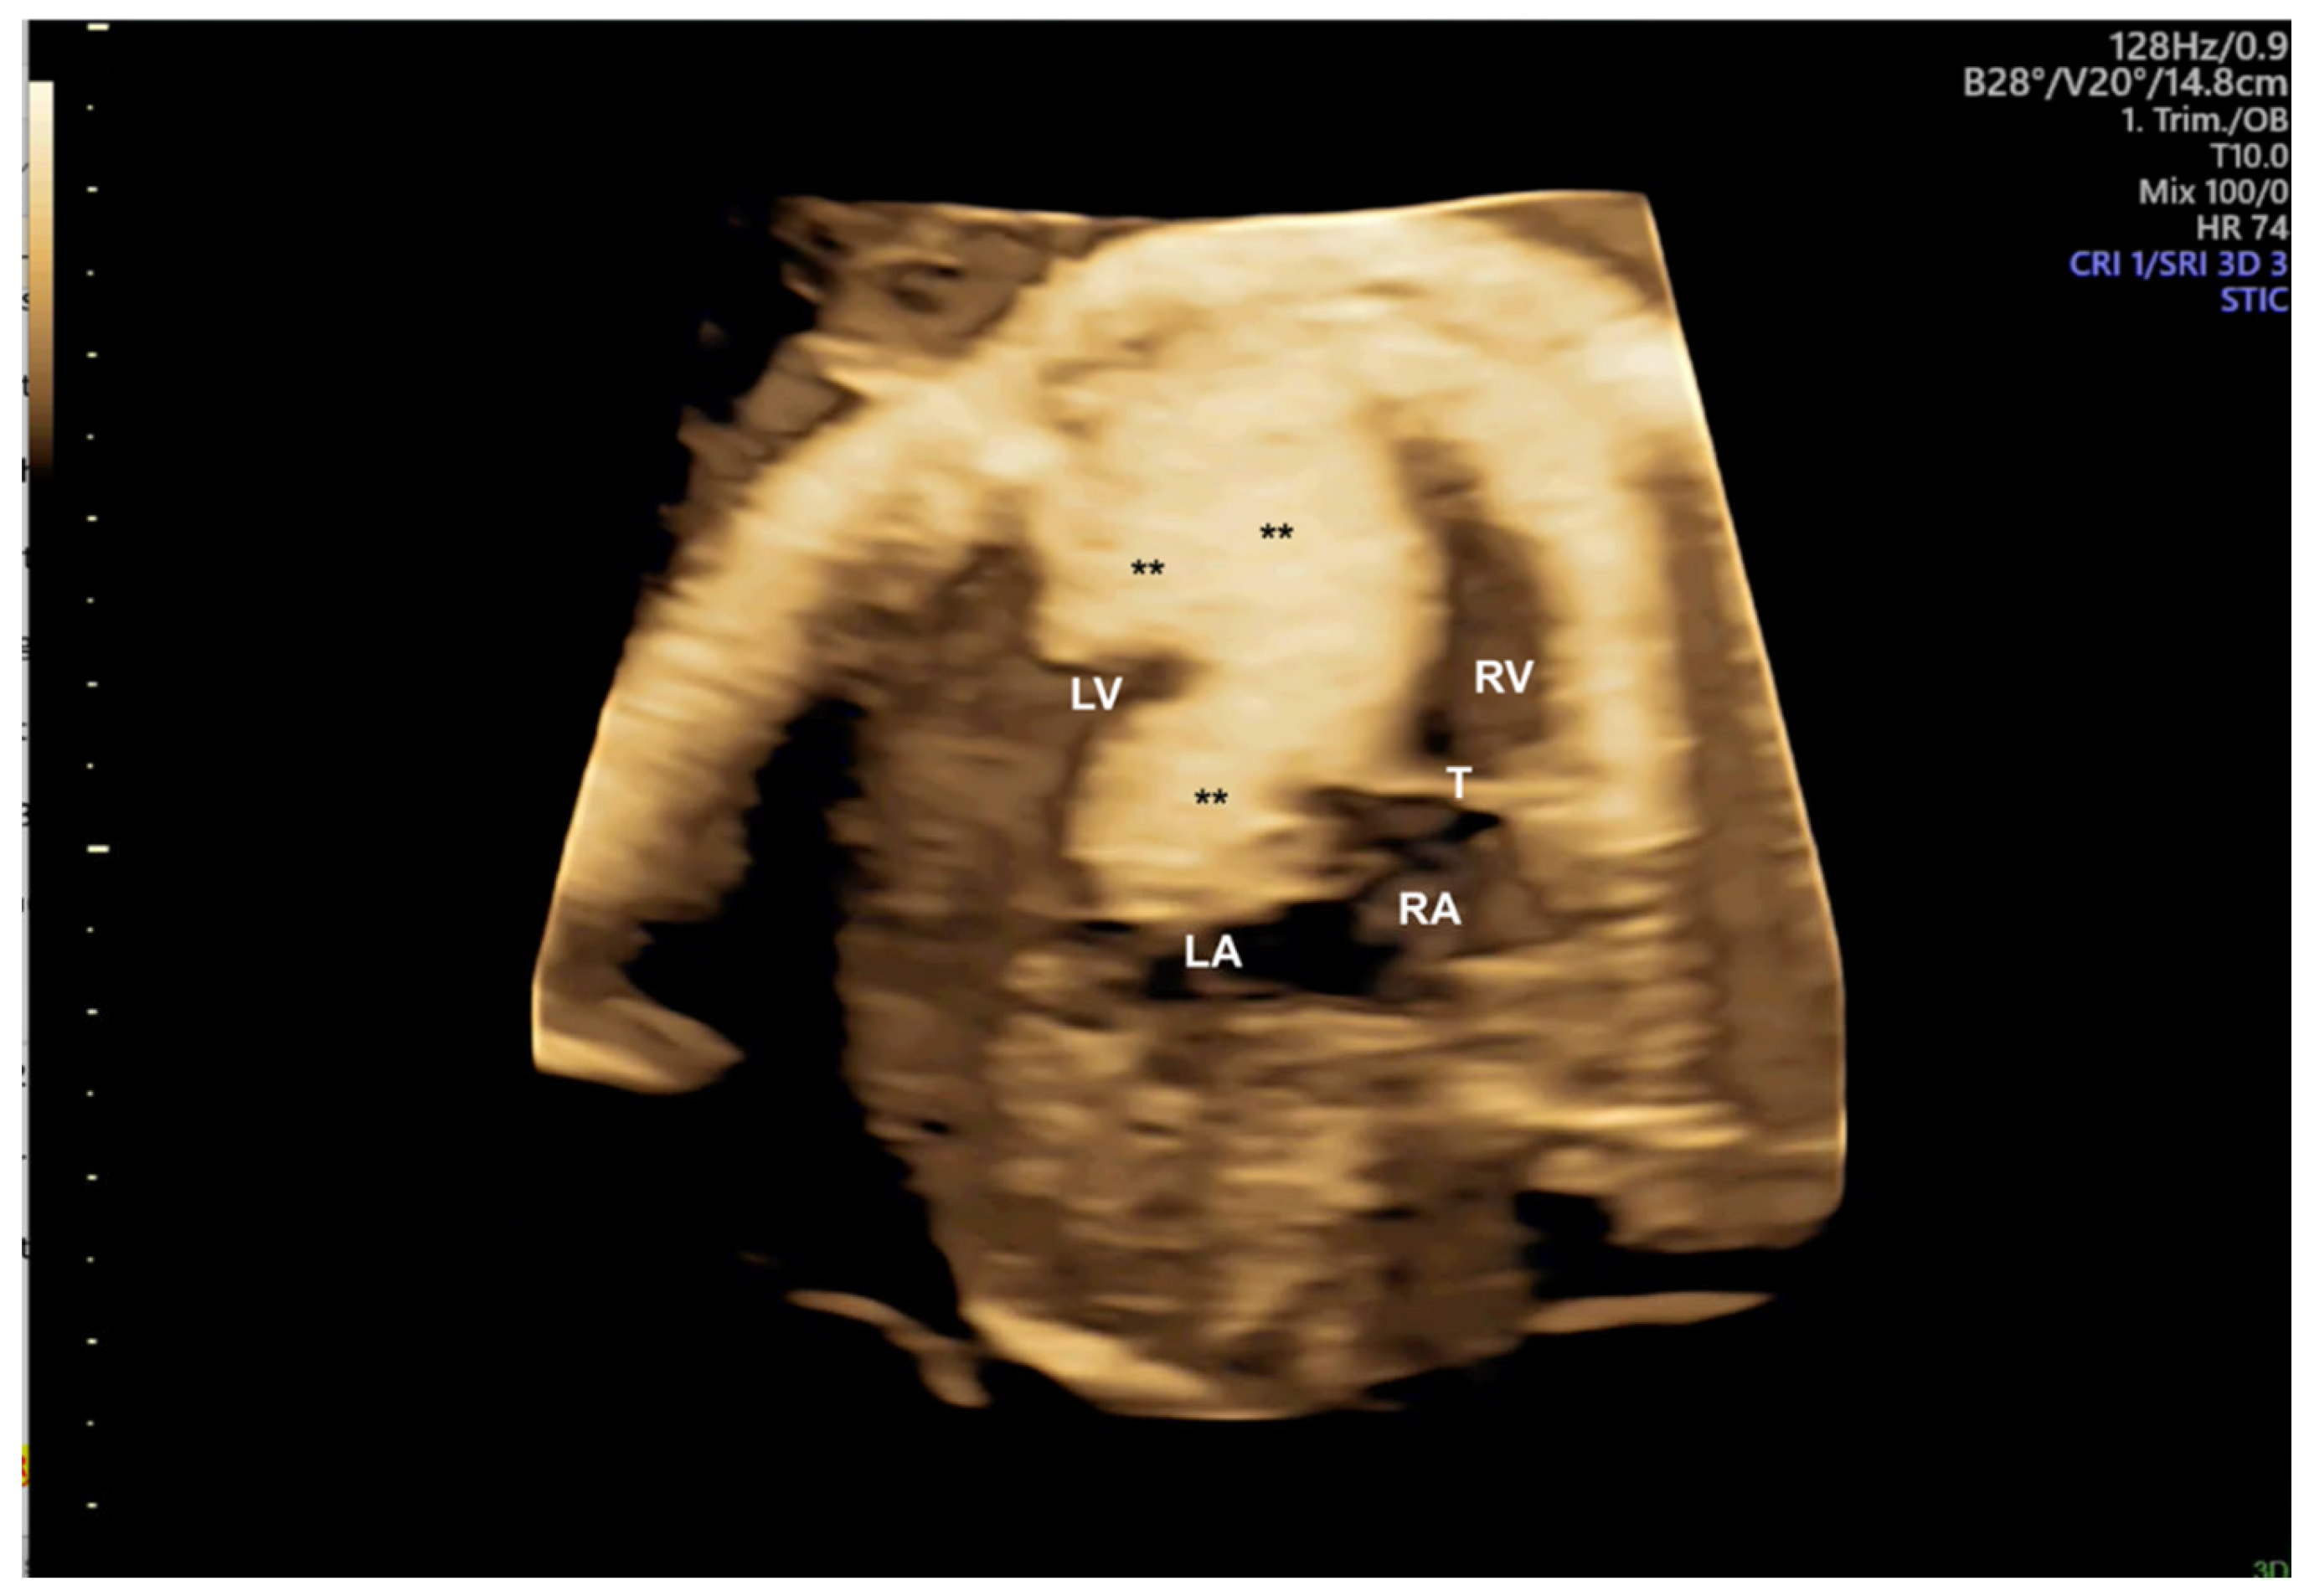

- Araujo Júnior E, Tonni G, Bravo-Valenzuela NJ, Da Silva Costa F, Meagher S. Assessment of Fetal Congenital Heart Diseases by 4-Dimensional Ultrasound Using Spatiotemporal Image Correlation: Pictorial Review. Ultrasound Q. 2018, 34, 11–17.

- Pontes ALS, Chagas CC, Bravo-Valenzuela NJ, Peixoto AB, Mappa I, Rizzo G; et al. Fetal heart foramen ovale area by three-dimensional ultrasound using stic in the rendering mode: Reference range and applicability in congenital heart diseases. Int J Cardiovasc Imaging. 2023, 39, 531–539.

- Pires GDV, Nieblas CO, Bravo-Valenzuela NJ, Araujo Júnior E, Castro PT, Werner H. Ebstein anomaly: 3D virtual and physical models from obstetrical ultrasound data. Echocardiography. 2024, 41, e15806.

- Malho A, Ximenes RS, Bravo-Valenzuela NJ, Araujo Júnior E. Spatio-Temporal Image Correlation: Three-Dimensional Imaging for Fetal Cardiac Screening and Congenital Heart Disease Assessment. Arq Bras Cardiol. 2024;121(4):e20230580.